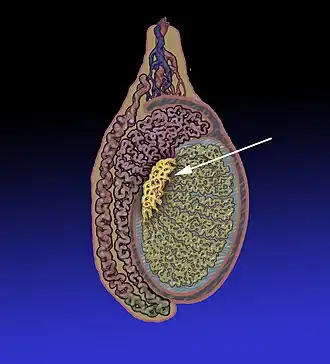

Posição do rete testis dentro do testículo.

| |

1: Septos do testículo

2: Túbulos seminíferos complicados 3: Lóbulos do testículo 4: Túbulos seminíferos retos 5: Dutos eferentes 6: Rete testis | |